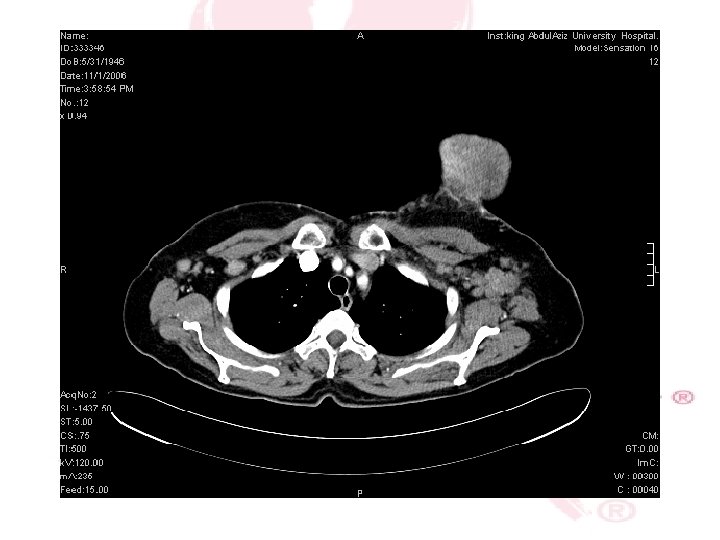

CT SCAN CHEST , ABDOMEN &PELVIS